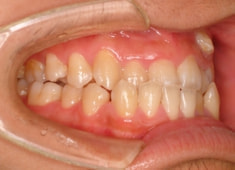

症例紹介

反対咬合+左上3番高位埋伏

(受け口+左上3番目の永久歯が上顎の中に埋まったままはえてきていない)

治療法:フルパッシブブラケット:T21

解説:残存している左上乳犬歯Cを抜歯し、そのスペースに左上3番を誘導しました。Cと犬歯ではスペースが足りないので、前歯をアドバンスさせ、反対咬合を同時に解消しております。

治療前